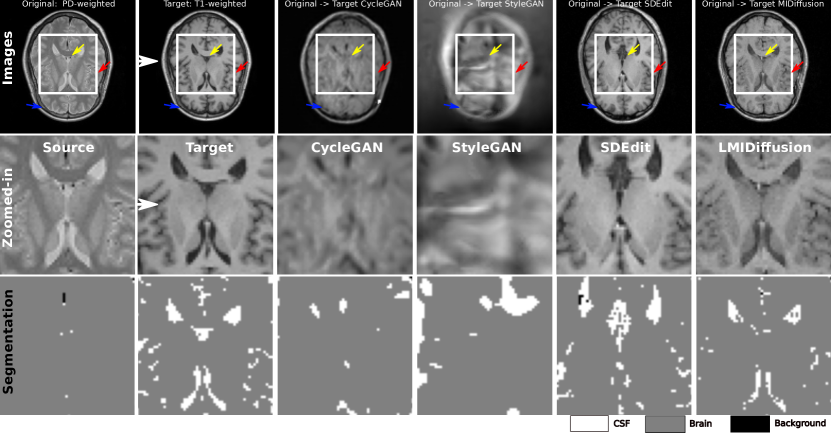

Figure 2: Qualitative evaluation of different models’ translation results. The first two rows show target and original modality images, with close-ups of ROIs, followed by transformations from CycleGAN, StyleGAN, SDEdit, and LMIDiffusion. The subsequent row displays binarized segmentation results in the ROIs using a 3 clusters K-Means method for segmentation, trained solely on the target modality.

Fig. 2 shows both the translation and segmentation outcomes from various models. The bottom rows provide a clear illustration of segmentation results based on translated images. Notably, the segmentation derived from LMIDiffusion translations closely mirrors the segmentation ground truth. While direct segmentation using a method trained on the target image is not feasible for the source domain image, our translation facilitates this, yielding commendable segmentation results on the translated image. Our approach not only offers maximal resemblance to the translation target (PDw) but also retains the superior anatomical features of the original modality (T1w). Although the CycleGAN is trained with supervised (few-shot) data, it fails to produce high-quality images. This shortcoming can be attributed to GAN-based models’ difficulty in discerning relationships between source and target modalities when training data from both domains is limited. On the other hand, while SDEdit does produce images in the PDw domain, it compromises the anatomical features of the original domain, rendering it less effective for zero-shot image segmentation.